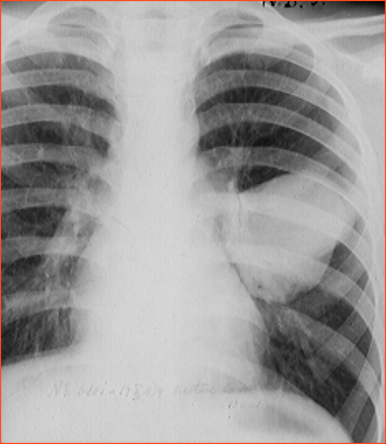

Rx toracică, incidență P-A

DESCRIERE: DAS + stază

indice cardiotoracic ↑

semne de dilatare a AS:

dublu contur inferior drept (contur dublu “festonat“)

deschiderea unghiului de bifurcație a traheei >120 grade

bombarea arcului mijl stg (golful pulm) → HTP

semne de stază pulm: dilatarea hilurilor + apicalizarea circulației + linii Kerley B

DX: stenoză mitrală

DD: insuf mitrală, boală mitrală, stenoză Ao